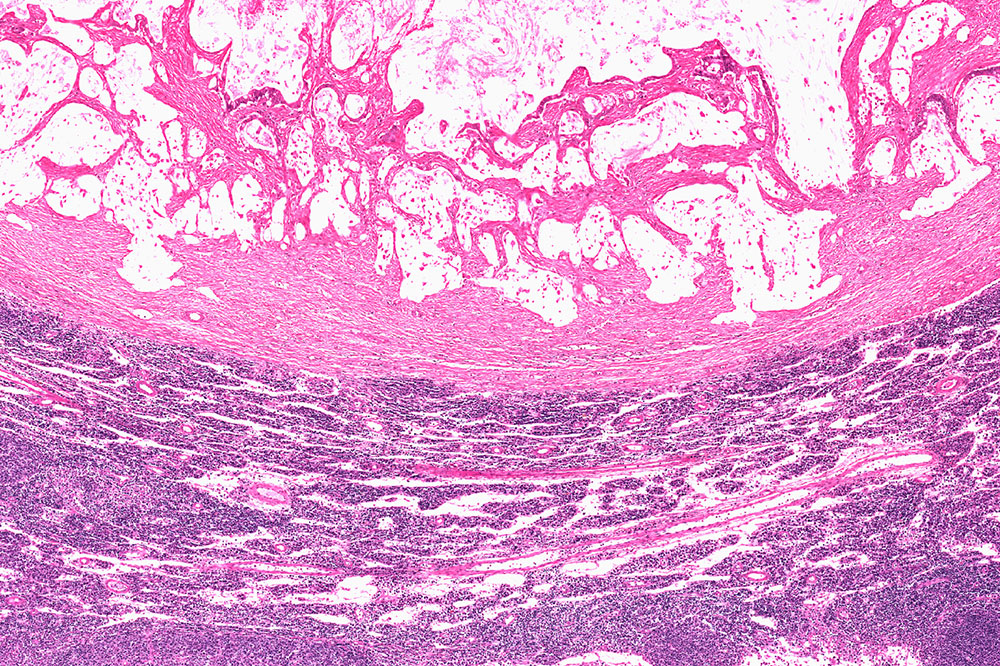

The condition, characterized by a malignant tumor, begins in the nerve cells of the digestive system. With time, they mutate and affect the normal functioning of the cells in the organ. Patients experience symptoms like anemia, abdominal pain, and vomiting, and these further aggravate if the condition is not treated. Therefore, ensure that you consult your doctor at the earliest.